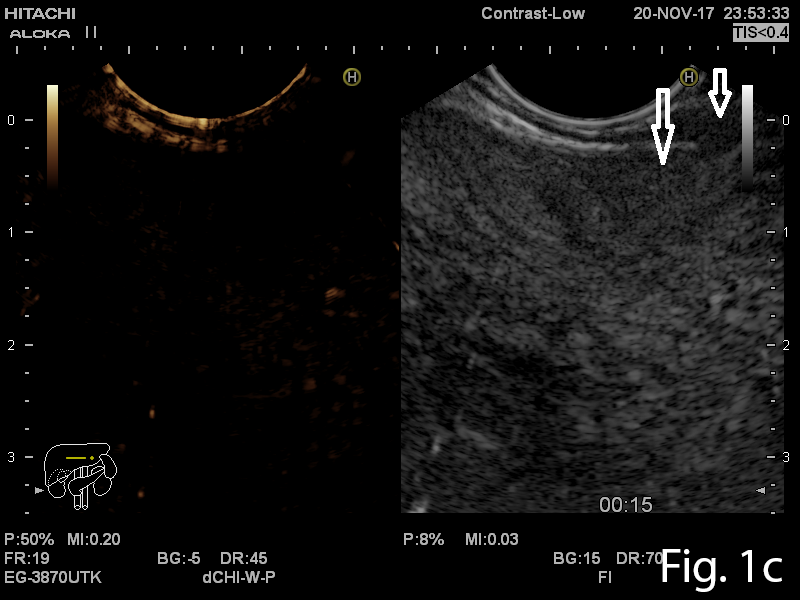

A 46-year old man presented to the gastrointestinal clinic complaining of dysphagia, regurgitation and a sensation of a lump in the throat, symptoms which had progressively worsened over the previous year. Upper GI endoscopy revealed a giant soft mass within the esophageal lumen, with a smooth surface covering, originating from the cervical esophagus, with a positive ”squeeze sign” (Video 1). EUS was performed and showed a giant mobile lesion occupying the esophageal lumen, with hyperechogenic structure, suggestive of a lipoma (Figure 1ab). Contrast-enhanced EUS did not depict any signals inside the subepithelial mass in the early arterial or late venous phases(Figure 1c). In order to define the surgical approach, a CT of the neck, thorax and abdomen was performed and it revealed the submucosal pedunculated tumor mass, confirming the diagnosis of lipoma (Figure 2).

Figure 1a-b. EUS showing a hyperechogenic lesion with a smooth margin arising from the submucosal layer of the esophagus. 1c. Contrast-enhanced EUS indicated completely absent signals, for both the early arterial and late venous phases.